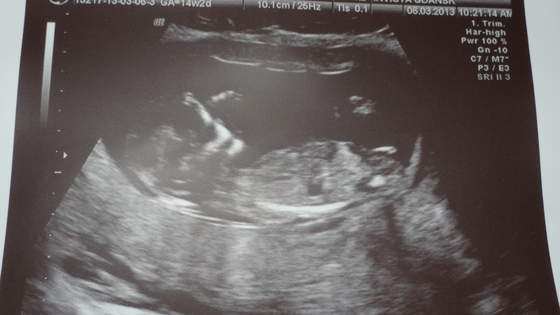

magdzia zdjęcie piękne, gratuluję udanej wizyty!